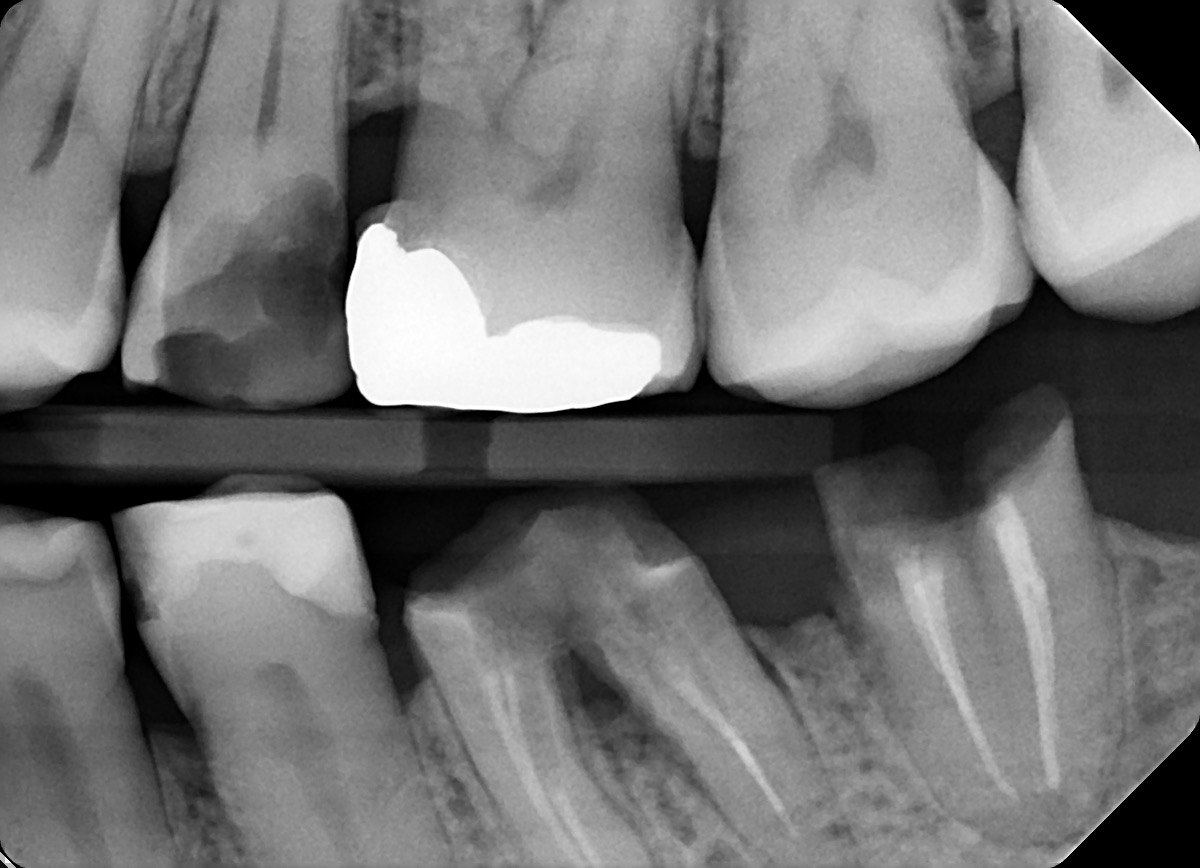

Question 33: What is the condition in mesial of tooth # 4.6?

Question 34: What is the level of caries on mesial of the tooth # 1.6?

Question 35: Which surface shows recurrent caries?

Question 36: What is the caries on distal surface tooth # 1.5?

37: What is the caries on mesial surface of tooth # 2.6 and distal surface of tooth # 2.5 respectivel?

38. What is the condition of the distal surface of tooth # 1.4 and mesial tooth surface tooth # 1.6?

39. What is the caries on distal tooth # 2.6 ?

40. What is the caries on mesial tooth #3.6 ?